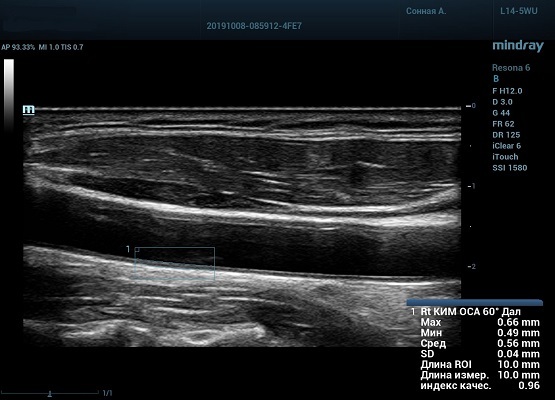

Auto IMT (автоматическое определение толщины комплекса интима-медиа)

Автоматическое измерение толщины передней и задней стенки, предоставляющее точную информацию о состоянии сонной артерии.